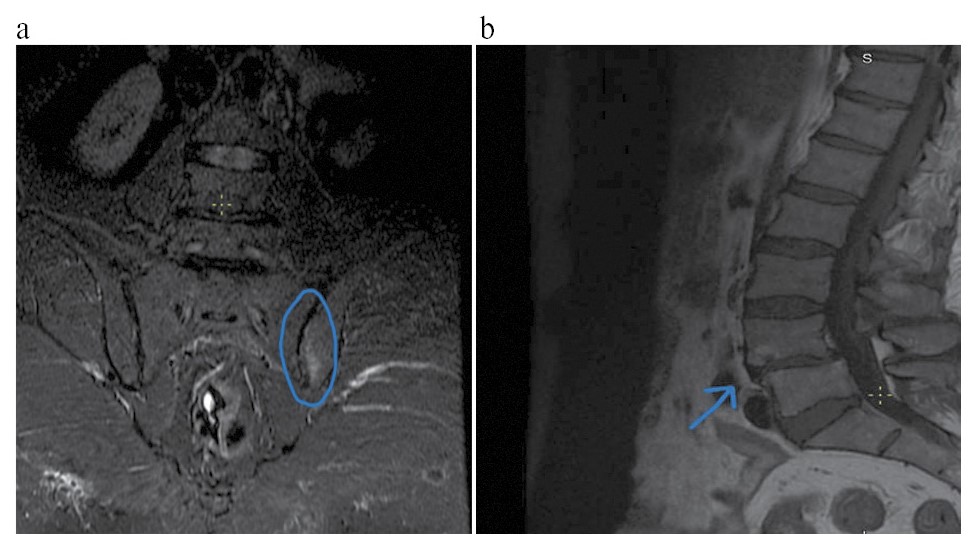

При объективном осмотре выявлен слабоположительный признак поперечной сдавливаемости кистей и стоп. При пальпации остистых отростков позвоночника отмечается болезненность. Сомнительный признак Кушелевского. Обнаружена болезненность при пальпации ахилловых сухожилий. Дактилиты III и I пальцев на левой кисти. Ограничение подвижности в плечевых и локтевых суставах. МТ пациента – 94 кг, рост – 166 см, ИМТ – 34,1, ОТ – 112 см. В лабораторных тестах уровень гемоглобина составил 107 г/л, скорость оседания эритроцитов (СОЭ) – 41 мм/ч, уровень СРБ – 66 мг/л, уровень глюкозы – 7,2 ммоль/л, уровни аспартатаминотрансферазы и аланинаминотрансферазы – в пределах нормы. Индекс Хома – 2,9. Гепатоспленомегалии по данным ультразвукового исследования не выявлено. Рентгенография таза с оценкой ТБС показала наличие состояния после интрамедуллярного остеосинтеза левой бедренной кости (рис. 1). Неполностью консолидированный межпозвонковый перелом. Остеоартроз левого ТБС 3-й степени. Асептический некроз головки правой бедренной кости в стадии фрагментации. Магнитно-резонансная томография (МРТ) грудного отдела позвоночника позволила выявить снижение высоты позвонков ThVII, ThVIII с умеренным отеком костного мозга в позвонке ThVII и формированием углового кифоза.

Рис. 1. Состояние после интрамедуллярного протезирования левой бедренной кости.

Fig. 1. Condition after intramedullary prosthesis of the left femoral bone.

В октябре пациент поступил для продолжения терапии ГИБП на фоне отсутствия обострения симптомов псориаза, несмотря на перерыв в приеме препаратов ГИБП. При объективном обследовании не выявлено симптомов поперечного сжатия кистей и стоп, остистые отростки позвоночника пальпаторно безболезненны, симптом Кушелевского 1-й степени отрицательный. Дактилиты III и I пальцев левой кисти находились в ремиссии. Ограничения в объеме движений в плечевых и локтевых суставах отсутствовали. Наблюдалась положительная динамика как по течению ПсА, так и по показателям лабораторных исследований: СОЭ – 6 мм/ч, СРБ – 10 мг/л, глюкоза – 5,8 ммоль/л, а также по показателям МС. Отмечены дальнейшее снижение МТ, ИМТ, ОТ, нормализация АД и гликемии натощак (см. рис. 1).

Рис. 4. Передний спондилит LIV–LV: a – фронтальная плоскость; b – сагиттальная плоскость.

Fig. 4. Anterior spondylitis LIV–LV: a – frontal plane; b – sagittal plane.